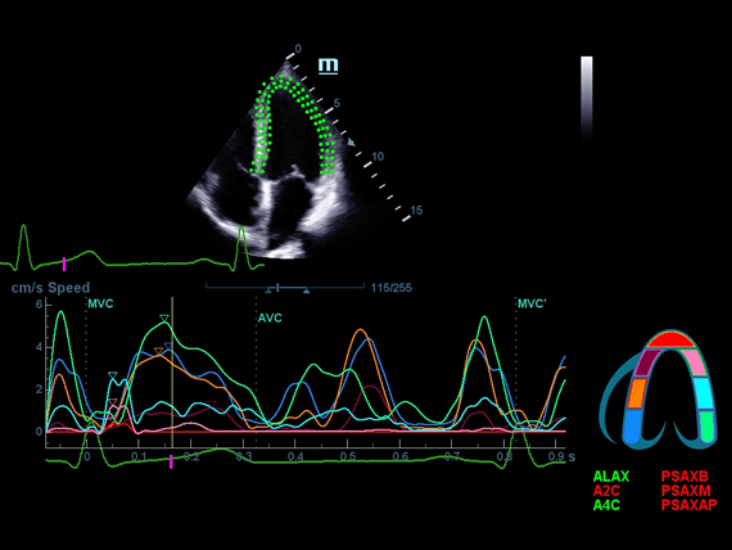

–°–Ņ–Ķ—Ü–ł–į–Ľ–ł–∑–ł—Ä–ĺ–≤–į–Ĺ–Ĺ—č–Ļ —É—Ö–ĺ–ī –Ī–Ľ–į–≥–ĺ–ī–į—Ä—Ź ECHO

–°–ĺ–≤–ľ–Ķ—Ā—ā–Ĺ–ĺ —Ā —Ā–ĺ–≤—Ä–Ķ–ľ–Ķ–Ĺ–Ĺ—č–ľ–ł —É–Ľ—Ć—ā—Ä–į–∑–≤—É–ļ–ĺ–≤—č–ľ–ł —ā–Ķ—Ö–Ĺ–ĺ–Ľ–ĺ–≥–ł—Ź–ľ–ł –Ĺ–ĺ–≤–ĺ–Ķ —Ä–Ķ—ą–Ķ–Ĺ–ł–Ķ –ĺ—ā Mindray –Ņ—Ä–Ķ–ĺ–Ī—Ä–į–∑—É–Ķ—ā –į–ļ—ā—É–į–Ľ—Ć–Ĺ—č–Ķ –∑–į–ī–į—á–ł –ļ–Ľ–ł–Ķ–Ĺ—ā–ĺ–≤ –≤ –ļ–Ľ–ł–Ĺ–ł—á–Ķ—Ā–ļ–ł–Ķ –Ņ–ĺ—ā—Ä–Ķ–Ī–Ĺ–ĺ—Ā—ā–ł. –ü–ĺ—Ā—ā–ĺ—Ź–Ĺ–Ĺ–ĺ —Ä–į–∑–≤–ł–≤–į—Ź—Ā—Ć, —ć—ā–į —Ā–ł—Ā—ā–Ķ–ľ–į —Ā–ĺ—á–Ķ—ā–į–Ķ—ā –≤ —Ā–Ķ–Ī–Ķ —Ā—ā—Ä–Ķ–ľ–Ľ–Ķ–Ĺ–ł–Ķ –ļ –Ĺ–Ķ–ĺ–≥—Ä–į–Ĺ–ł—á–Ķ–Ĺ–Ĺ—č–ľ –≤–ĺ–∑–ľ–ĺ–∂–Ĺ–ĺ—Ā—ā—Ź–ľ –ł –∂–Ķ–Ľ–į–Ĺ–ł–Ķ –∑–į–≥–Ľ—Ź–Ĺ—É—ā—Ć –≤ –Ī—É–ī—É—Č–Ķ–Ķ.

–ú–Ĺ–ĺ–≥–ĺ—Ą—É–Ĺ–ļ—Ü–ł–ĺ–Ĺ–į–Ľ—Ć–Ĺ–į—Ź —Ā–ł—Ā—ā–Ķ–ľ–į DC-60 Exp —Ā X-Insight –Ņ—Ä–Ķ–ī—Ā—ā–į–≤–Ľ—Ź–Ķ—ā —Ā–ĺ–Ī–ĺ–Ļ –ļ–ĺ–ľ–Ņ–Ľ–Ķ–ļ—Ā–Ĺ–ĺ–Ķ —Ä–Ķ—ą–Ķ–Ĺ–ł–Ķ, –ļ–ĺ—ā–ĺ—Ä–ĺ–Ķ –Ņ–ĺ–ľ–ĺ–≥–į–Ķ—ā —É–Ņ—Ä–į–≤–Ľ—Ź—ā—Ć –Ņ–ĺ–≤—Ā–Ķ–ī–Ĺ–Ķ–≤–Ĺ–ĺ–Ļ –ļ–Ľ–ł–Ĺ–ł—á–Ķ—Ā–ļ–ĺ–Ļ –Ņ—Ä–į–ļ—ā–ł–ļ–ĺ–Ļ —Ā –Ľ–Ķ–≥–ļ–ĺ—Ā—ā—Ć—é –ł —É–≤–Ķ—Ä–Ķ–Ĺ–Ĺ–ĺ—Ā—ā—Ć—é.

–ě—Ā–Ĺ–ĺ–≤—č–≤–į—Ź—Ā—Ć –Ĺ–į –≥–Ľ—É–Ī–ĺ–ļ–ĺ–ľ –Ņ–ĺ–Ĺ–ł–ľ–į–Ĺ–ł–ł –Ņ–ĺ—ā—Ä–Ķ–Ī–Ĺ–ĺ—Ā—ā–Ķ–Ļ –ļ–Ľ–ł–Ķ–Ĺ—ā–ĺ–≤, –ļ–ĺ–ľ–Ņ–į–Ĺ–ł—Ź Mindray —Ä–į–∑—Ä–į–Ī–ĺ—ā–į–Ľ–į —Ā–ł—Ā—ā–Ķ–ľ—É DC-60 Exp —Ā X-Insight, —á—ā–ĺ–Ī—č –ĺ–Ī–Ķ—Ā–Ņ–Ķ—á–ł—ā—Ć –≤—č—Ā–ĺ–ļ—É—é –Ņ—Ä–ĺ–ł–∑–≤–ĺ–ī–ł—ā–Ķ–Ľ—Ć–Ĺ–ĺ—Ā—ā—Ć –ł —ā–ĺ—á–Ĺ–ĺ—Ā—ā—Ć –≤–ł–∑—É–į–Ľ–ł–∑–į—Ü–ł–ł –≤–ļ—É–Ņ–Ķ —Ā –Ĺ–į–≥–Ľ—Ź–ī–Ĺ–ĺ—Ā—ā—Ć—é, –ł—Ā–ļ–Ľ—é—á–ł—ā–Ķ–Ľ—Ć–Ĺ–ĺ–Ļ –ł–Ĺ—ā–Ķ–Ľ–Ľ–Ķ–ļ—ā—É–į–Ľ—Ć–Ĺ–ĺ—Ā—ā—Ć—é –ł –ĺ–≥—Ä–ĺ–ľ–Ĺ—č–ľ –ĺ–Ņ—č—ā–ĺ–ľ.